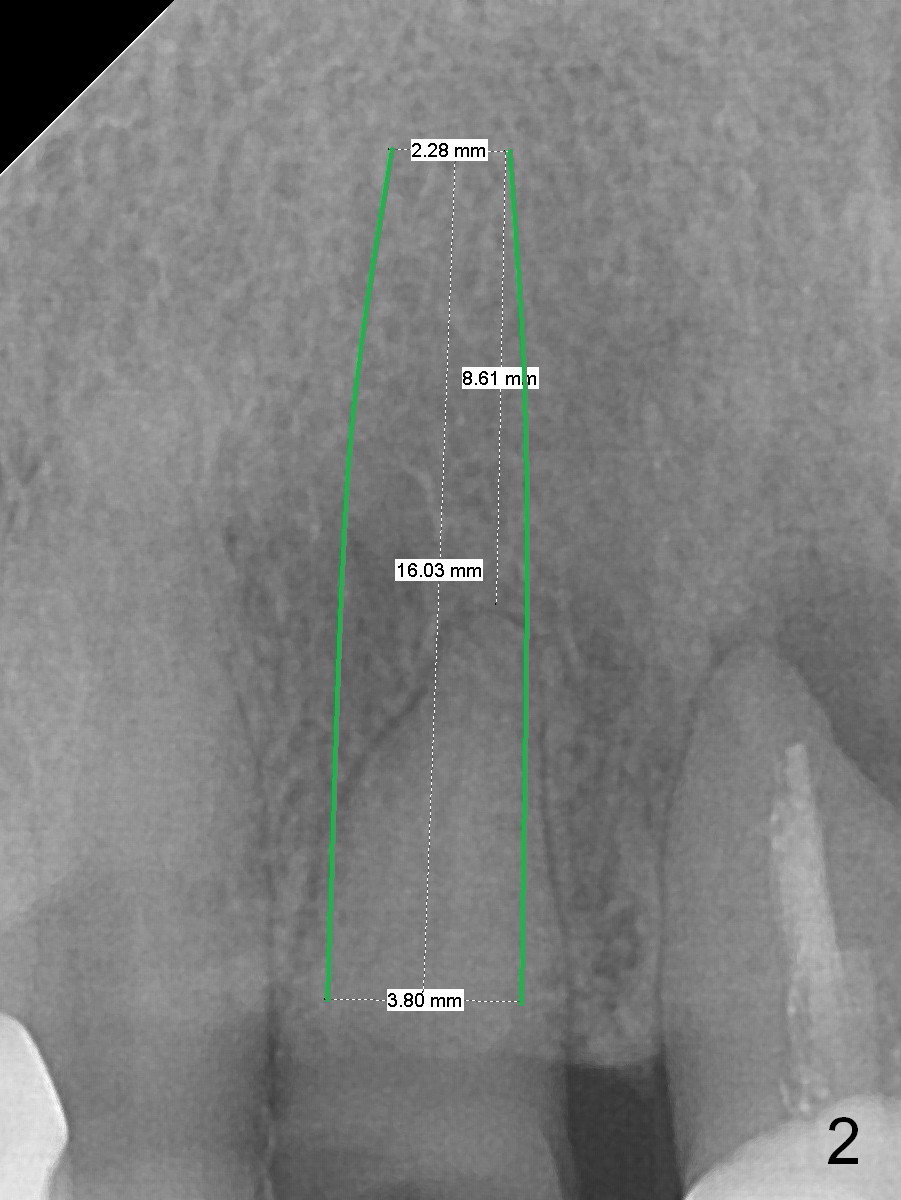

A 60-year-old woman has multiple restoration and no lower posterior teeth (replaced with RPD). The tooth #7 fractures (Fig.1). When an immediate implant is placed (Fig.2, no Antibiotic) with immediate provisional (using the existing crown), occlusal clearance is critical. Check overbite often and take photos. If the root seems to be ankylosed, socket shield will be performed.

In fact the residual root (Fig.3) is easy to remove. A 3.8x16 mm implant is placed (Fig.4 (with 2 mm buccal gap)) at the level as planned (Fig.2). Insertion torque is acceptable. After placing a 4.5x5(3) mm gold-coated abutment and allograft (Fig.5), an immediate provisional is fabricated (the existing crown is lost). The patient is pleased with the quick, painless procedure.